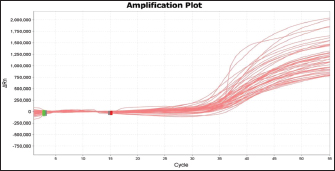

Fig. 2. Blood smear indicates Mycoplasma haemofelis invades equine RBCs. Fluorescent microscopy,0.1% acridine orange staining. 1000X. qPCR resultIn the current study, 79%(79/100) of diseased horses were found to be positive using qPCR (Figs. 3 and 4). The agreement between the two diagnostic methods was analyzed using Cohen's Kappa statistic. The observed agreement was 91% (91/100), and the expected agreement by chance was 72.04%. The calculated Kappa coefficient was κ=0.678 (95% CI), indicating substantial agreement between cytological and qPCR diagnoses according to the Landis and Koch benchmark Table 1.

Fig. 3. Amplification plot of the 16S rRNA gene of Mycoplasma haemofelis positive samples.